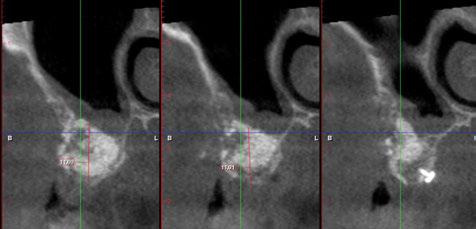

Para ilustrar el proceso, presentamos el caso de una mujer joven diagnosticada de carcinoma adenoide quístico en la región posterior del hemipaladar izquierdo (Figuras 1 y 2). El procedimiento quirúrgico realizado fue una

maxilectomía parcial que incluyó las piezas 24-26 y desde el reborde alveolar hasta la base del cráneo (Figuras 3 y 4). En este caso, la órbita y el globo ocular pudieron ser preservados. La reconstrucción inmediata se realizó mediante un colgajo de músculo temporal homolateral (Figura 5) y el defecto de la fosa temporal fue cubierto mediante una malla de titanio. Posteriormente, la paciente recibió radioterapia (Figuras 6 y 7). 2 años más tarde se diseñó un IS con anclaje en el arbotante nasomaxilar, zona subnasal izquierda

y lo que se pudo preservar del hueso malar. Se añadió una malla sinterizada infraorbitaria para dar volumen a la mejilla y se planificaron dos brazos de conexión que emergieran en las posiciones 24 y 26 de forma subgingival (Figuras 8 y 9). La superficie interna que apoyaba en el hueso era de titanio microrrugoso, y la superficie externa y conectores de titanio pulido y hexágono externo universal (Figuras 10 y 11). La cirugía se hizo bajo anestesia general en infiltración con anestesia local (4% articaína, 1:100.00 epinefrina), levantando el

colgajo cutáneo de la mejilla por vía intraoral, preservando el colgajo temporal para no comunicar con el remanente de la cavidad naso maxilar (Figura 12). Se emplearon 10 tornillos de osteosíntesis de 1,9 mm y la estabilidad primaria obtenida fue excelente (Figura 13)

8. Imagen 3D de la extirpación y planificación del implante subperióstico.

Posición de los tornillos de osteosíntesis y emergencia de las conexiones.

Figura

Figura 9.